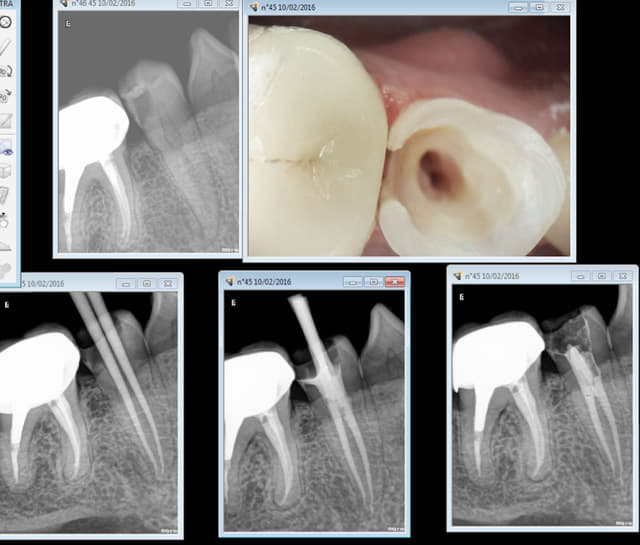

Ici pas de digue, j'ai toute confiance dans le succès de mon tt endo. Avec digue ca n'aurait rien changé.

C'est pas de la salive qu'il y a autour du cone de gutta mais du naocl + de chez coltène ! -)

Capture d e cran 2016 02 10 13.50 - Eugenol